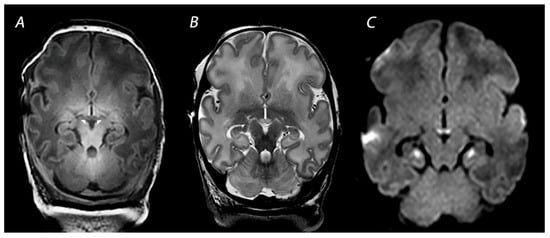

2.1. Basal Ganglia and Thalami (BGT) Predominant Pattern of Injury